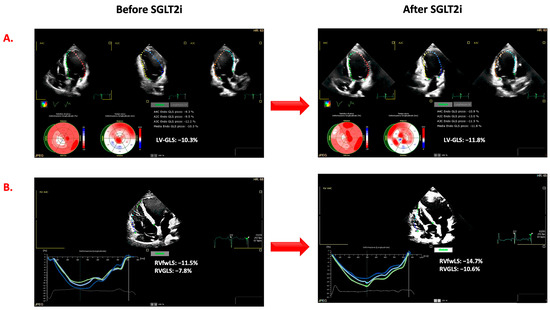

- Echocardiographic examinations. Echocardiographic examinations were analyzed by two operators (G.A., R.P.) who were in the blind from the time of the evaluation as well as from the results of the other examinations of each patient. In accordance with current recommendations, LVEF was calculated on the basis of left ventricular end-diastolic volume (LVEDV) and end-systolic volume (LVESV) (Simpson’s rule). The ratio between E and e′ (E/e′) was based on the peak of the E wave (E) at pulsed Doppler and the TDI peak of early diastolic velocity peak (e′) at the level of the septal and lateral mitral annulus [18]. Mitral (MR) and tricuspid (TR) regurgitation were evaluated and quantified by arbitrary units (a.u. range from 0 to 4). Tricuspid annular plane systolic excursion (TAPSE) was assessed in order to evaluate RV systolic function. As shown in Figure 1, the strain measurements were obtained by the AutoStrain application of the Philips EPIQ CVx ultrasound system. From the “off-cart” analysis of the stored examinations, the LV global longitudinal strain (LV-GLS) was measured by the analysis of standard two-, three-, and four-chamber views and the average values of all segments. Using the RV-focused four-chamber view, the RV function was assessed by automatically calculating the global longitudinal strain of the right ventricle (RV-GLS) and that of the free wall (RV-fwLS). Although the AutoStrain application allows for semiautomatic evaluation, the region of interest, the automatically detected cardiac cycle, and the segmental analyses’ accuracy were verified and corrected when appropriate. Ventricular strain measurements are expressed as negative values, i.e., the lower the value, the better the ventricular function. For this reason, in the manuscript, we indicated more negative values than those determined at baseline as improved ventricular systolic strain. LV reverse remodeling was defined as a reduction of LVESV greater than 15% from baseline [19], whereas a significant improvement in LVEF was defined as an absolute increase of more than 5% from baseline. The improvement in LV-GLS, RV-GLS, and RV-fwLS was defined as a relative change of more than 10% from baseline [20].